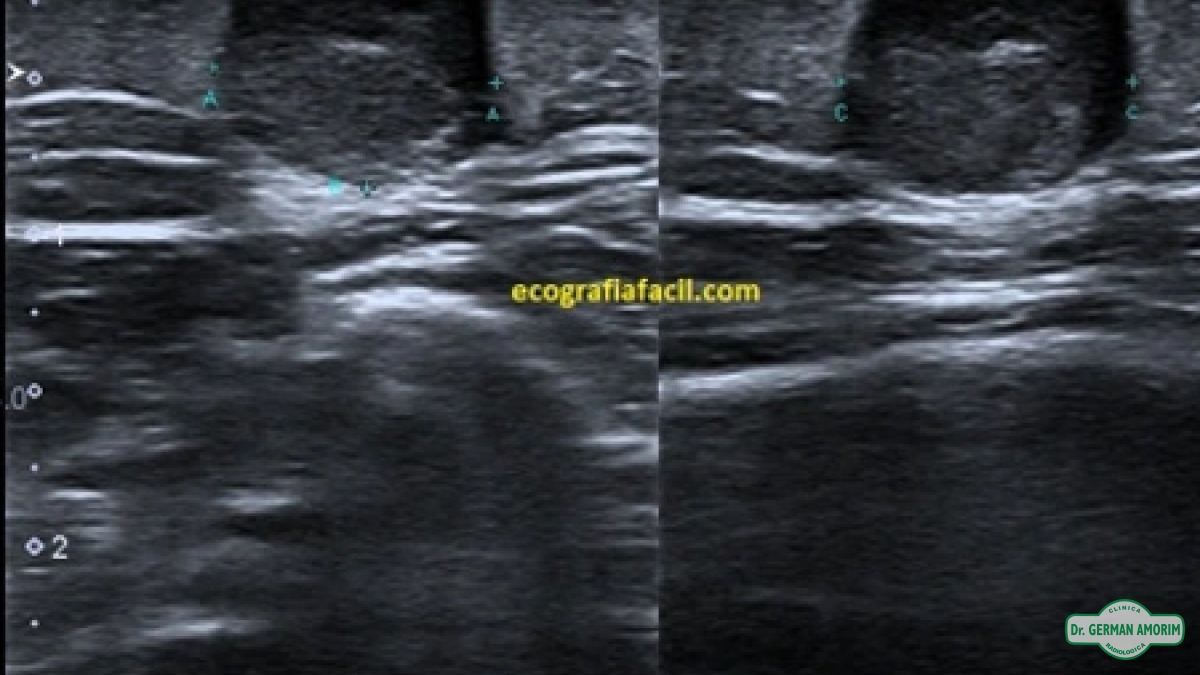

Las imágenes por ultrasonido involucran el uso de un pequeño transductor –similar a un micrófono conectado por un cable- y un gel que será aplicado sobre la zona a examinar.

El transductor recogerá los sonidos por medio de rebote y una computadora utilizará estas ondas sonoras para generar la imagen (sistema similar al de los murciélagos y barcos).

Fuentes: Soc. Chilena de Radiología, .org, Ecografiafacil.com